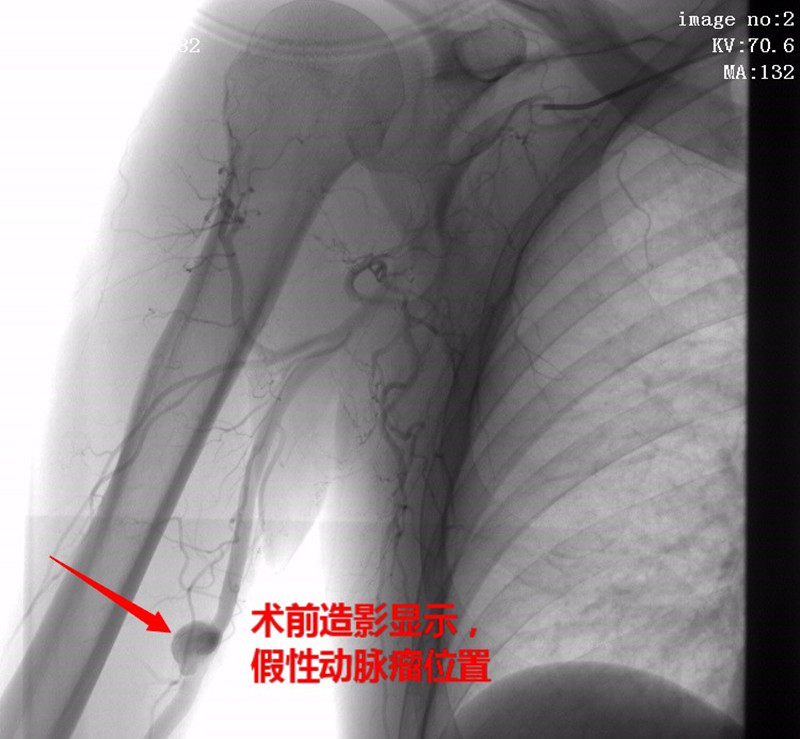

2020年3月5日来我院超声检查示:右侧肱动脉假性动脉瘤。次日,CT血管成像示:右侧肱动脉中段见一直径约13mm结节状高密度影,呈明显强化影,广基底。诊断结果: 右侧肱动脉假性动脉瘤。查体:右侧肱骨中段触及一搏动性包块,活动度差。

经我院外周介入科积极完善术前准备,于3月12日在DSA下为该患者行“右侧颈内动脉造影、右上肢动脉造影+右肱动脉假性动脉瘤覆膜支架腔内隔绝术”。术后查体:右侧肱骨中段触及包块,搏动性消失,听诊无杂音,包块缩小。

术前